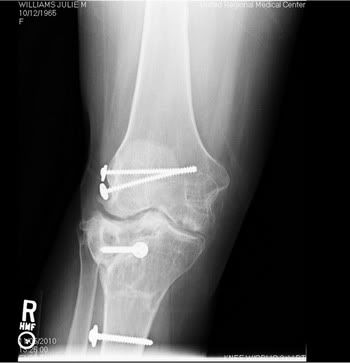

Most people don't understand why I am the way I am. I hope these x-rays give them a better idea of what I have to deal with every single day.

My right knee: